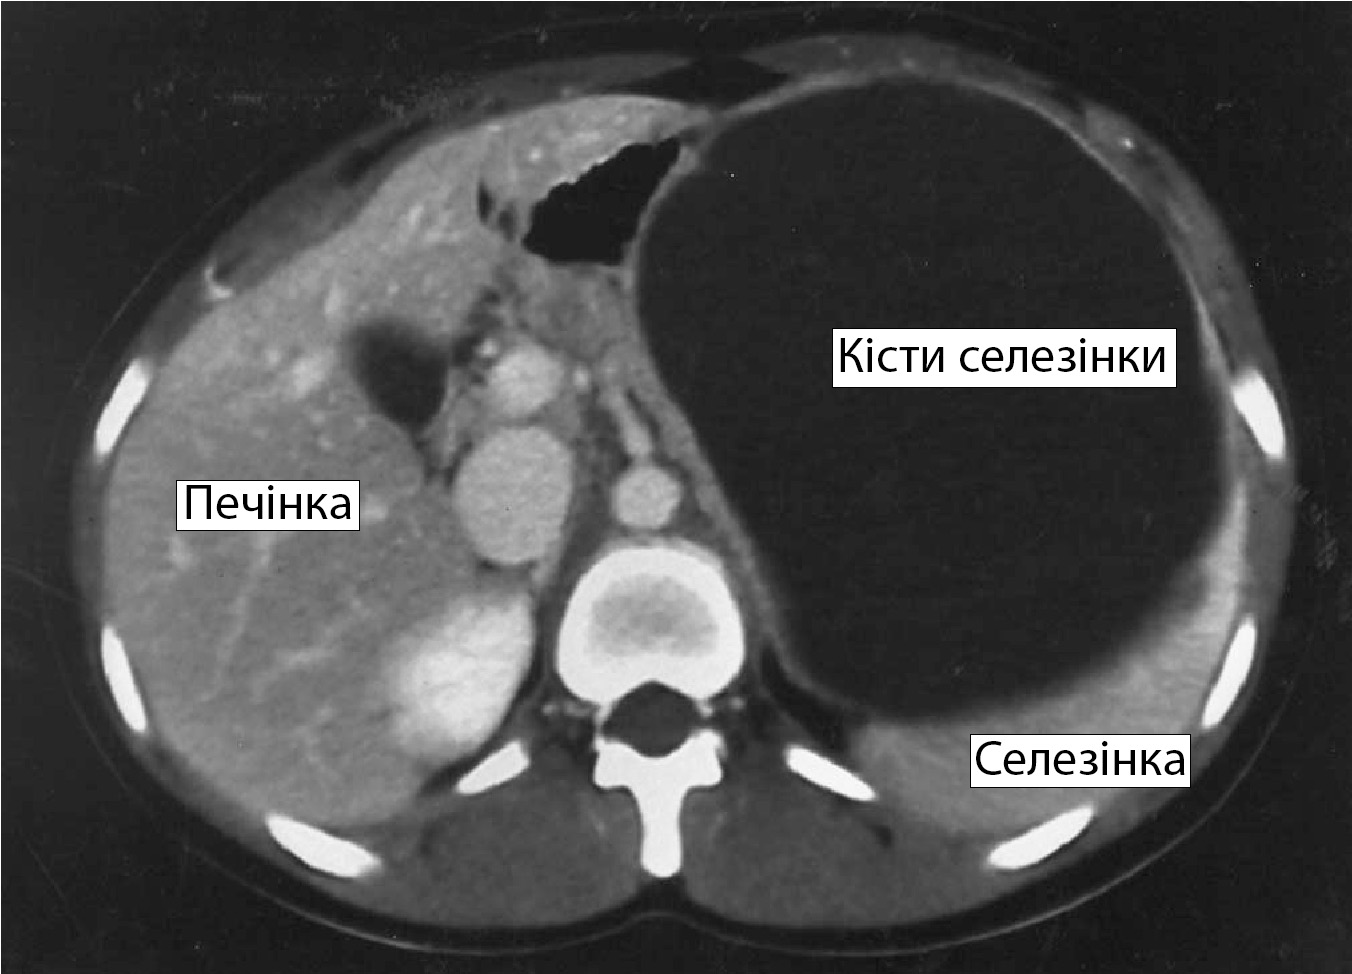

Клиническая картина такого заболевания схожа с проявлениями других патологий желудочно-кишечного тракта. Поэтому для диагностики состояния обращаться нужно к гастроэнтерологу. Для установления диагноза врачи проведут УЗИ диагностику. Метод позволяет определить локализацию, размер, структуру кисты в селезенке. При необходимости назначается компьютерная или магнитно-резонансная томография.

При множественных дефектах врач оценивает размер общей пораженной области. В случае, когда образования занимают больше 50% площади селезенки, работоспособность органа сильно ухудшается.